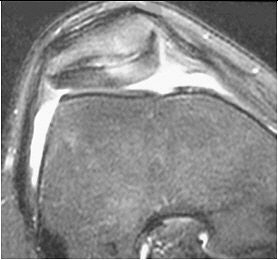

| MRI demonstrates cartilage abnormality in the patella of a cyclist. Courtesy of Duke University Medical Center, Musculoskeletal Division, Durham, NC. |

Overall, the most common problem is patellofemoral disease, which accounts for as much as 25% of all cycling injuries, according to experts.

"The overwhelming presenting injury these cyclists have is patellofemoral disease -- chondromalacia or cartilage issues in the patellofemoral joint," said Dr. Nancy Major, associate professor of radiology at Duke University in Durham, NC. "Even the tendon can get something called ‘jumper’s knee,’ which is commonly seen in basketball players."